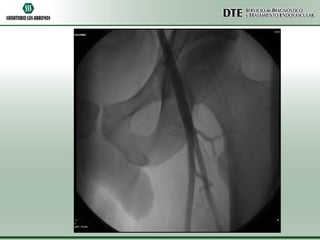

ATPP

•Utilizando una guía hidrofílica de 0.035” se atravesó la obstrucción total crónica y

sobre la misma guía se avanzó un catéter cobra 5F el cuál fue posicionado a nivel del

tronco peroneo.

•Se realizó un test angiográfico a dicho nivel, no comprobándose permeabilidad. No

se visualizaron el llenado de las arterias tibial anterior, tibial posterior ni peronea.

•Se intercambió la guía hidrofílica por una guía de 0.014” y utilizando un catéter de

trombo aspiración Export 6F, se realizó trombo aspiración mecánica a nivel del

segmento ocluido.

•Se logró aspirar gran cantidad de material trombótico fresco, a pesar de lo cuál no

pudo recanalizarse exitosamente la obstrucción total.

•Debido al riesgo de comprometer con microembolias la circulación colateral, se

decidió dar por terminado el procedimiento.

•El control angiográfico final demostró una sensible mejoría a nivel de la circulación

colateral con un llenado más rápido de la arteria pedia y el arco plantar.

ATPP •Utilizando una guíahidrofílica de 0.035” se atravesó la obstrucción total crónica y sobre la misma guía se avanzó un catéter cobra 5F el cuál fue posicionado a nivel del tronco peroneo. •Se realizó un test angiográfico a dicho nivel, no comprobándose permeabilidad. No se visualizaron el llenado de las arterias tibial anterior, tibial posterior ni peronea. •Se intercambió la guía hidrofílica por una guía de 0.014” y utilizando un catéter de trombo aspiración Export 6F, se realizó trombo aspiración mecánica a nivel del segmento ocluido. •Se logró aspirar gran cantidad de material trombótico fresco, a pesar de lo cuál no pudo recanalizarse exitosamente la obstrucción total. •Debido al riesgo de comprometer con microembolias la circulación colateral, se decidió dar por terminado el procedimiento. •El control angiográfico final demostró una sensible mejoría a nivel de la circulación colateral con un llenado más rápido de la arteria pedia y el arco plantar.